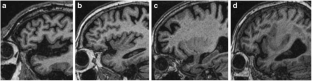

Fig. 1

Fig. 2

Fig. 3